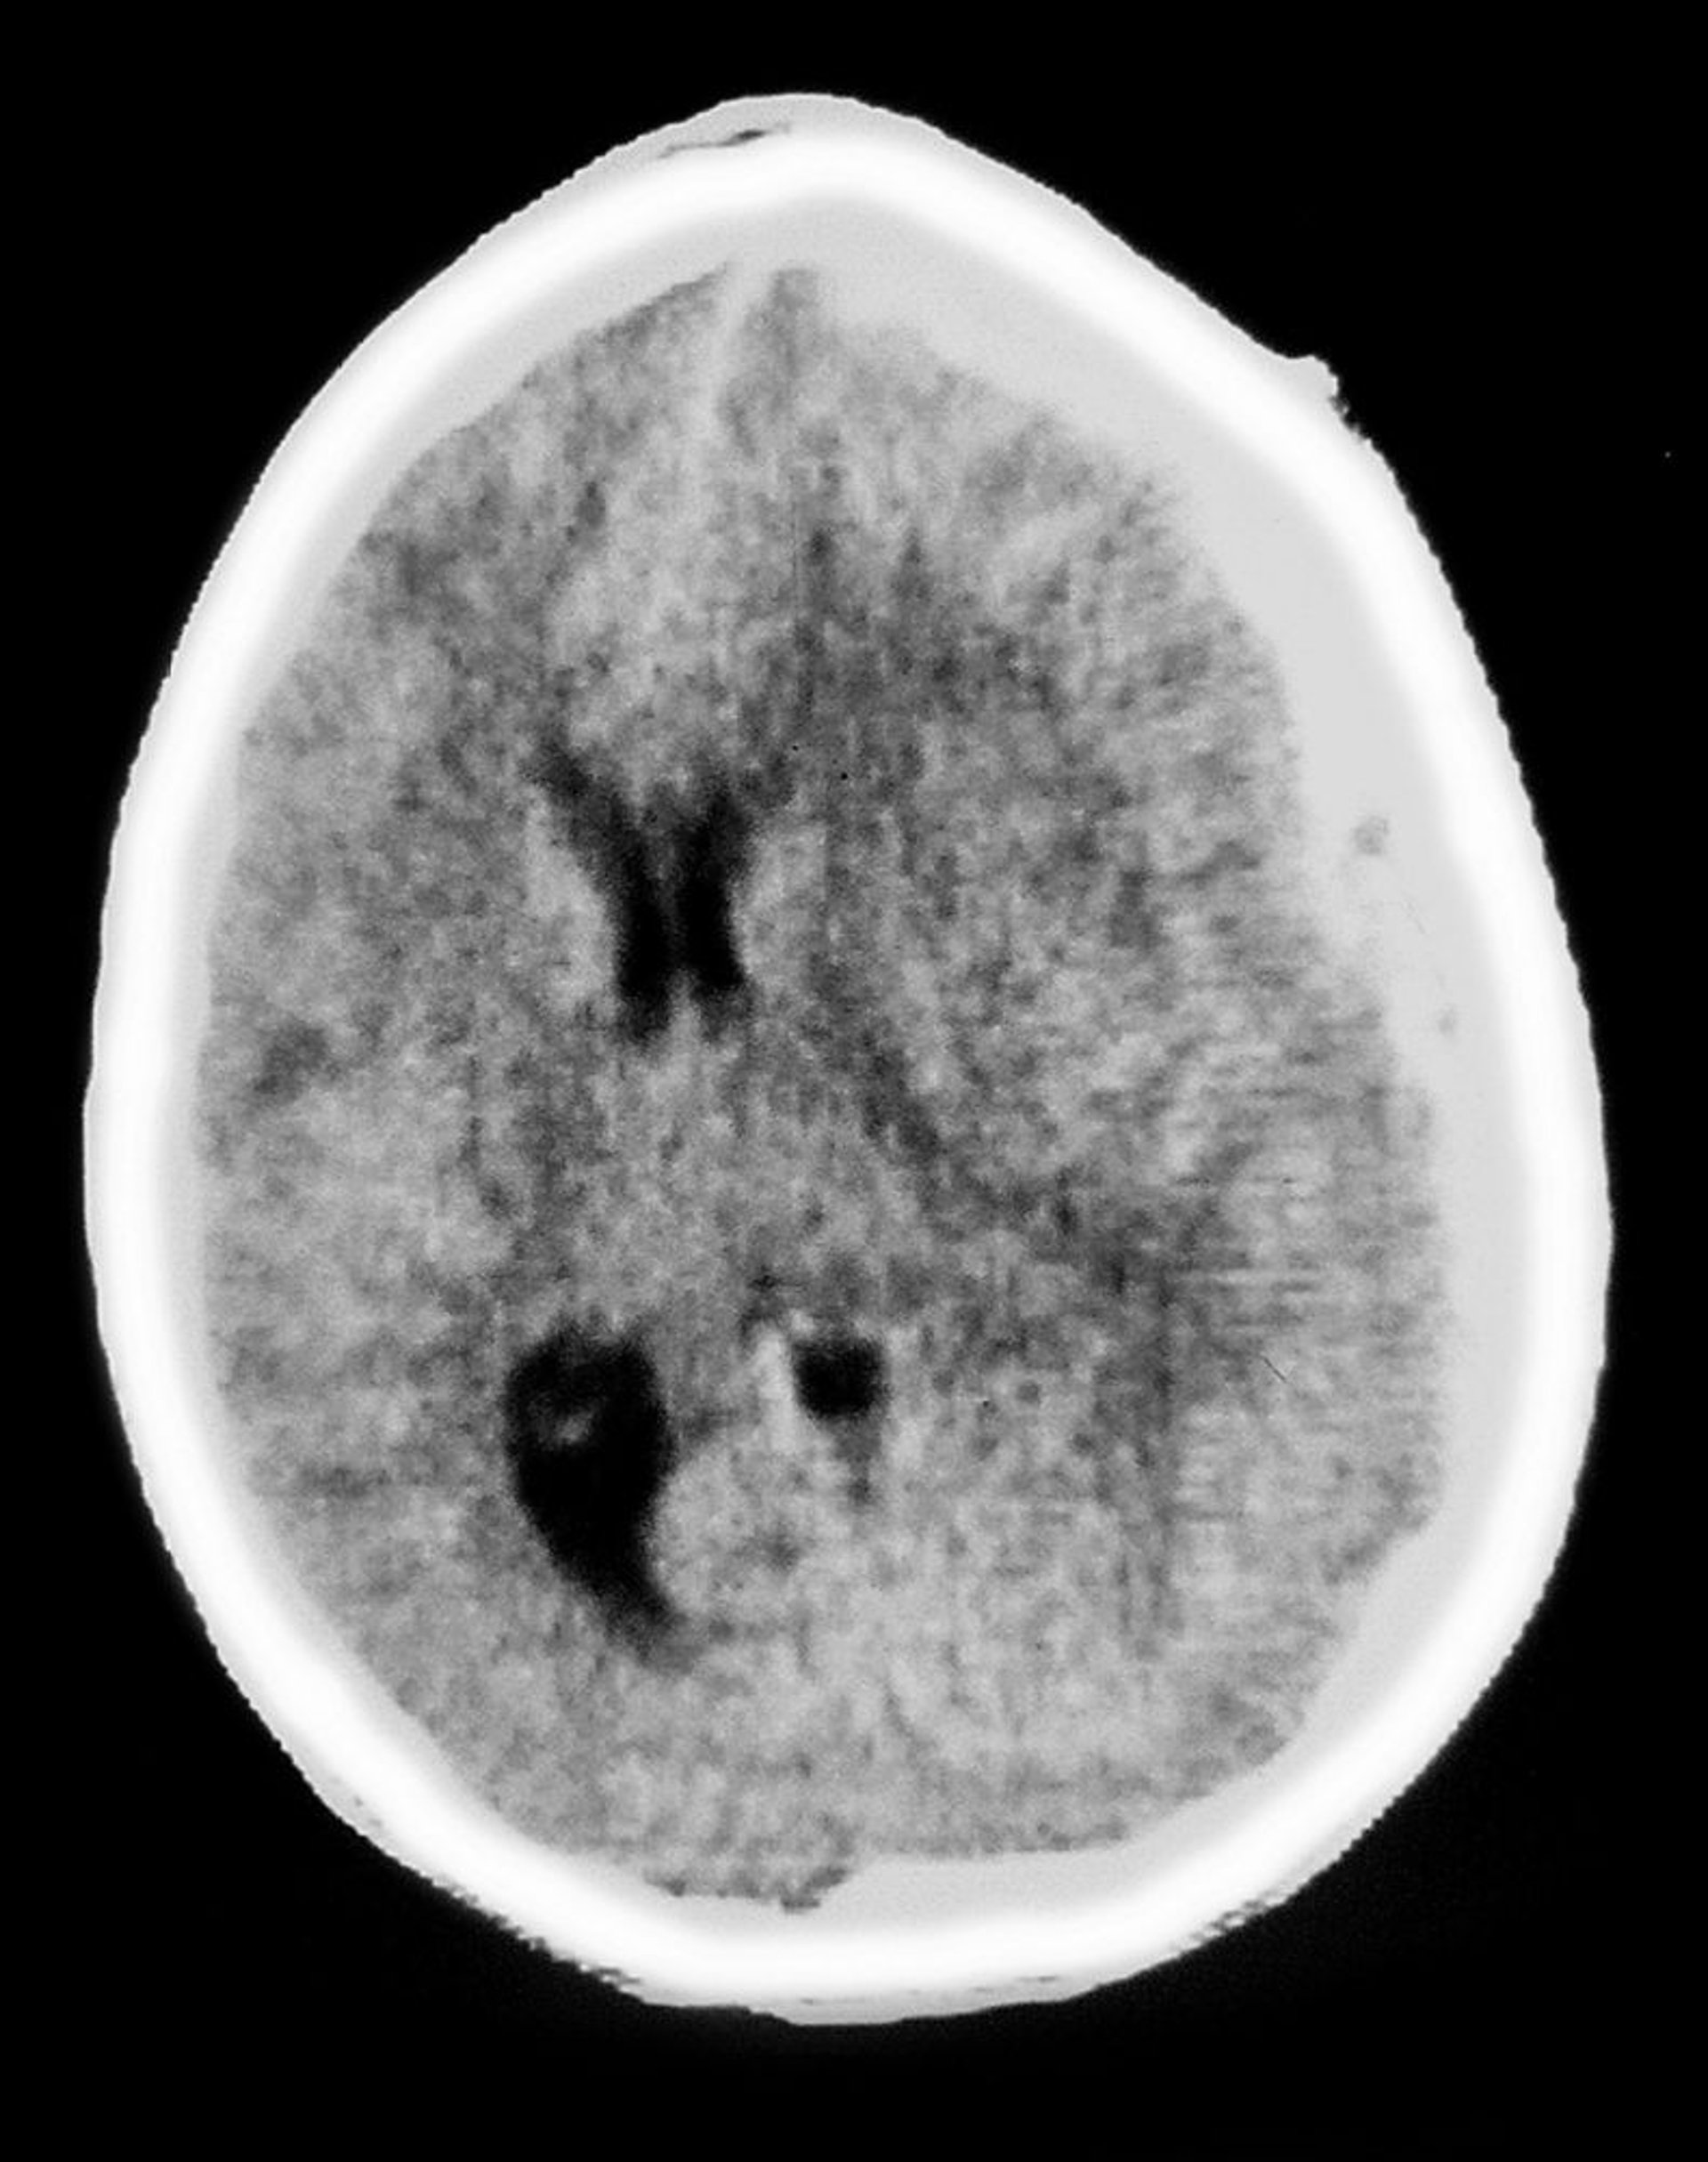

硬膜下血腫

このCTには,脳組織を覆う半月状の陰影が写っている。これは硬膜下血腫の特徴である。腫瘤効果(mass effect)もみられ,脳室の圧迫および正中偏位を伴う。